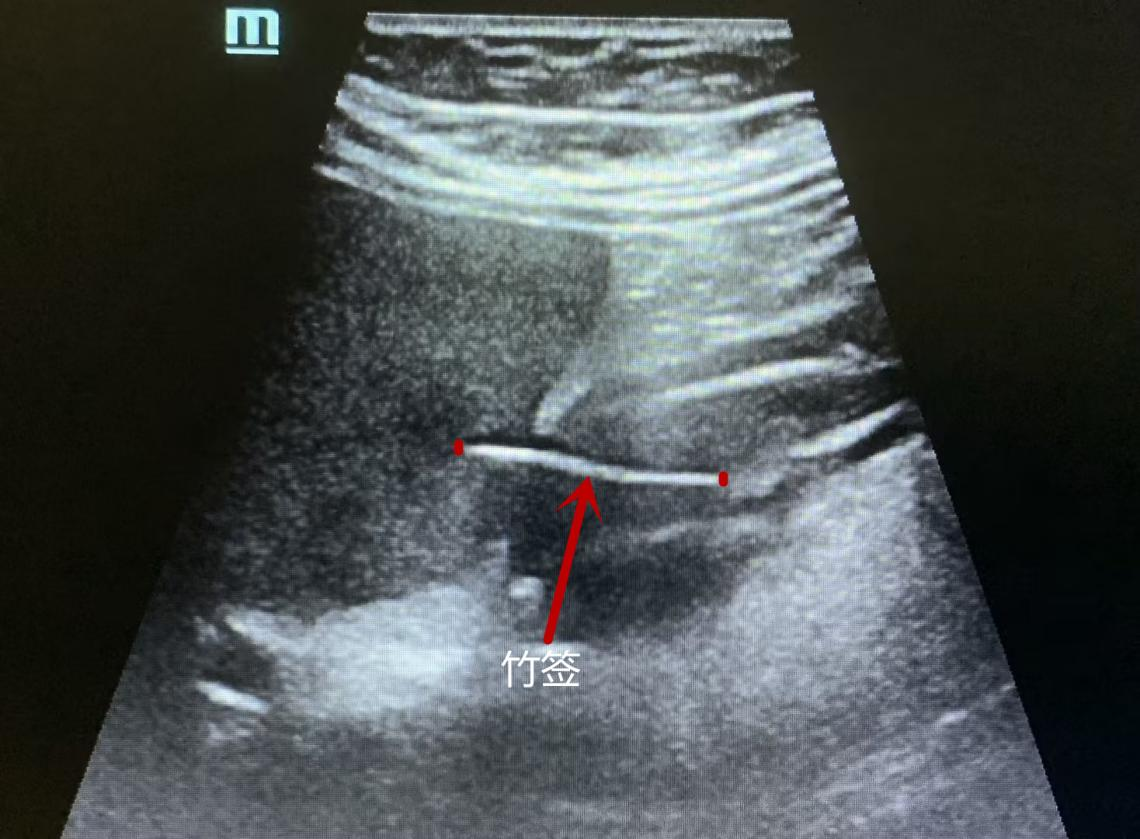

超声科谭庆亭医师反复检测,在患者的胃窦处发现了一个细细长长的异物,经张华斌主任当场会诊后,明确了诊断。此时,患者才努力地回想起,自己发病的前一天曾用竹签吃过包子。超声检查发现这根竹签已经刺破了胃壁,扎入了肝脏。“胃镜没发现是因为这根竹签的位置很特殊,它穿出了黏膜层,位于黏膜下。”超声科主任张华斌解释说。

图片3.png

张华斌主任讲解异物的位置

而CT和PET/ CT作为临床判别肿瘤的重要手段,主要依靠对组织密度和代谢情况的识别来得出结果,对金属类异物很敏感,但对于竹制品这类与人体软组织密度相似的异物却很难辨别出来。“这根小竹签无论是质地还是位置,对于医学检查来说都十分‘狡猾’。局部增厚的胃壁、肝脏的局灶低回声,以及周围的淋巴结,这些都是异物引起的炎性反应,容易判别为肿瘤倾向。”张华斌解释说。